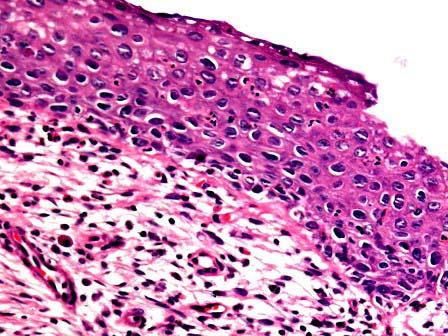

问题 女性,34岁,接触性出血一年余加重一周,行子宫切除,显微镜下见鳞状上皮细胞具异型性,异型细胞超过上皮全层2/3,但不及3/3。如图,应诊断为 ( )

选项 A.CINⅠ级 B.CINⅡ级 C.CINⅢ级 D.原位癌 E.浸润癌

答案 C